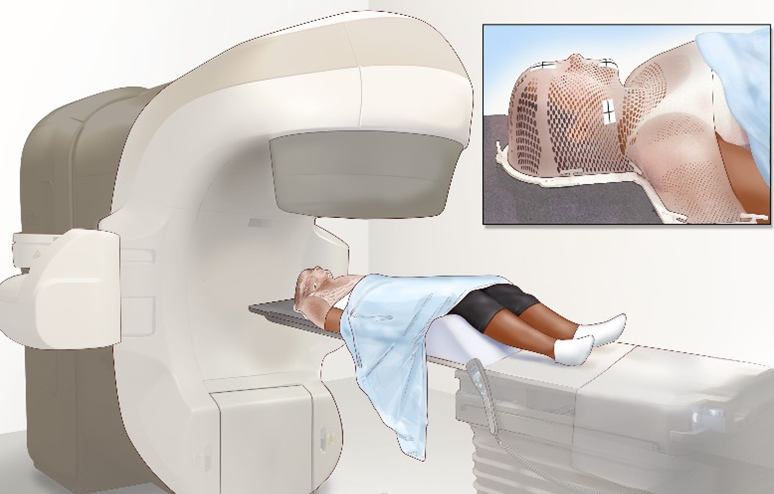

- Лучевая терапия

- Дистанционная лучевая терапия при опухолях головного мозга используется как самостоятельный метод либо после хирургического удаления/биопсии опухоли, при возникновении рецидива/продолженного роста опухоли.

- Проводится в конвенциальном (стандартном) или конформном режиме облучения, непрерывным или расщеплённым курсом.

- Оптимальной методикой является применение конформных техник облучения, что позволяет осуществить максимально безопасное подведение дозы на область опухоли с минимально возможной лучевой нагрузкой на здоровые ткани. При планировании облучения пациентов с опухолями головного мозга проводят разметку с помощью мультиспиральной КТ, при возможности формируют индивидуальное фиксирующее устройство – термопластическую маску.

- Дистанционная лучевая терапия назначается при наличии морфологически подтвержденной злокачественной опухоли, а также диагноза, поставленного на основе клинико-лабораторных и инструментальных исследований, в первую очередь учитывающих результаты КТ, МРТ и ПЭТ.

Схематичное изображение аппарата мультиспиральной КТ и индивидуального фиксирующего устройства (термопластическая маска)